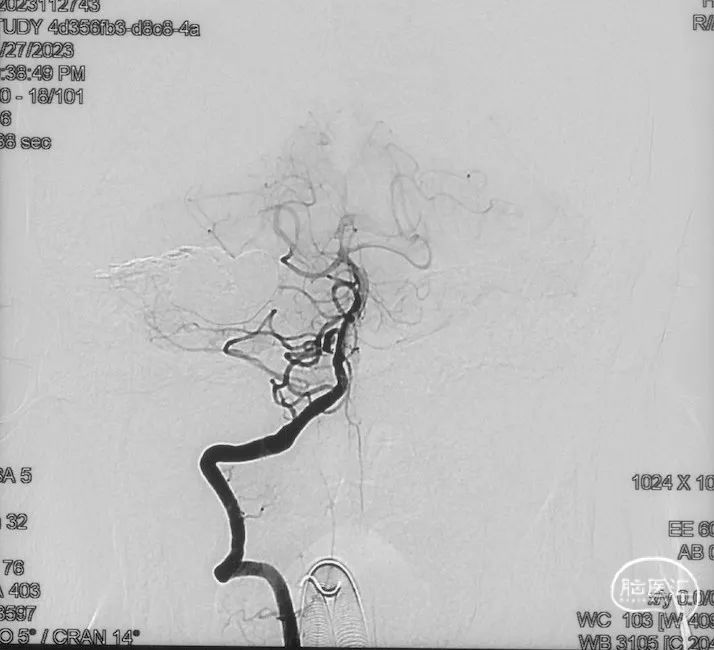

影像学的随访

术后9m

右侧颈内动脉造影未见瘘口显影及静脉早显

右侧颈外动脉造影未见瘘口显影及静脉早显

左侧椎动脉造影未见瘘口显影及静脉早显